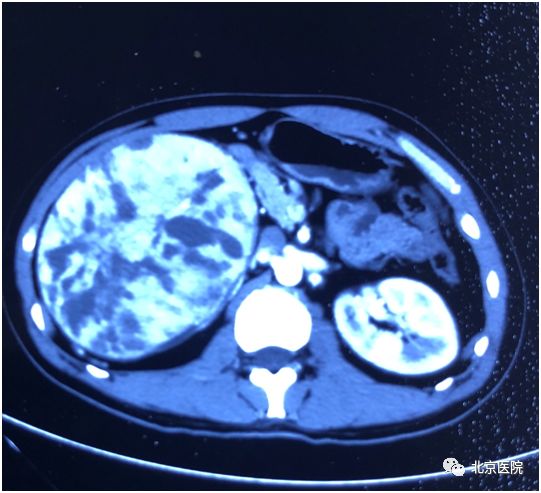

肾细胞癌是泌尿系统最常见的肿瘤之一,约占肾脏恶性肿瘤的80%-90%。近日,北京医院泌尿外科收治一名年轻男性患者,两周前自行摸到其右侧腹部有一包块,无疼痛感。遂到医院检查B超提示:右肾占位,进一步CT增强扫描提示右肾巨大占位,最大径约18cm,体积为正常肾脏8倍之大,考虑恶性,全身评估未见转移病灶,需手术根治切除治疗。但因肿瘤巨大侵犯肾脏包膜,与周围脂肪组织黏连,且肿瘤血供丰富,表面多发迂曲小静脉、质脆,术中不易剥离,容易引发大出血,增加了手术难度和风险。

术前CT显示肾脏肿瘤状态